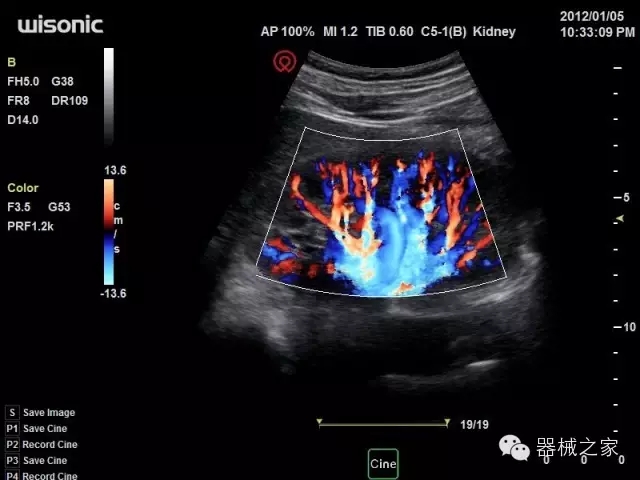

臨床圖片賞析

產(chǎn)品特點(diǎn)

·全球目前唯一一款配備主機(jī)雙探頭接口,整機(jī)重量(含電池)在5公斤以內(nèi)的便攜式彩超;

·一款互聯(lián)網(wǎng)彩超,只要有手機(jī)信號(hào)的地方就可以非常方便地實(shí)現(xiàn)遠(yuǎn)程會(huì)診和病案調(diào)?。?/span>